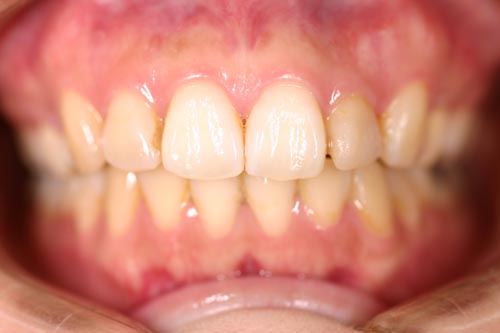

50代で歯周病のもある患者様の矯正症例

Before

特に奥歯が抜いてあるため、奥歯の本数がこれ以上少なく出来ない方です。これだけの強い不正咬合を非抜歯で治した症例です。年齢的にも難しい症例でしたが、かなりきれいに治り、 患者様自信が大変満足された症例です。

年齢 50代

治療期間 1年6ヶ月

治療費用 1,000,000円

治療のリスク 歯周病が進行するリスクがある